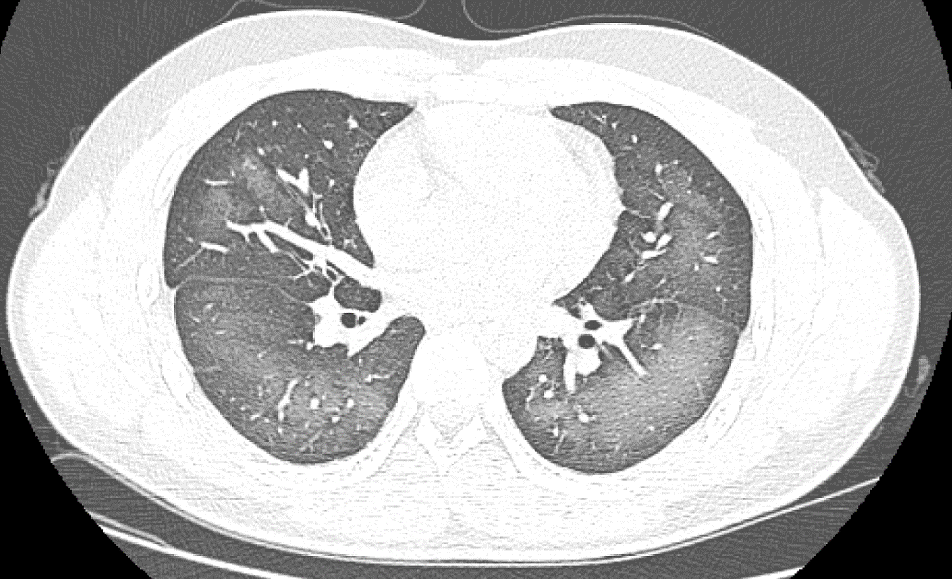

장사시의 20살 청년 리림(가명)은 외출하기 전에 자외선 차단 스프레이를 사용했는데 얼굴에 살포할 때 부주의로 코로 흡입했다. 바로 가슴이 답답해나고 기침 증세가 나타났다. 증상이 이튿날까지 계속되면서 호전을 보이지 않자 그는 급히 호남성 장사시 제3병원을 찾아 진료를 받았다. 검사 결과, 페 CT 영상에서 뚜렷한 넓은 범위의 흰색 모양 병변을 볼 수 있었고 보고서에는 “백색페증"이라는 진단이 적혀 있었다.

“백색페증”은 일반적으로 중증페염이 X선이나 CT검사에서 나타나는 것을 말하는데 환자의 페부는 넓은 흰색 상태를 보이고 흔히 호흡곤란, 호흡부전이 나타나며 엄중한 경우에는 기타 장기기능 장애도 나타난다.

장사시 제3병원 방사선영상과 진료의는, 감염, 확산성 페포출혈증후군 등 "백색페증"의 가장 흔한 병인 외에 분진, 분무 등 유해물질을 흡입할 경우 페부에 넓은 범위의 흰색모양의 병리변화가 나타날 수 있다고 밝혔다. 젊은 환자는 부적절한 사용으로 인해 자외선 차단제의 일부를 페로 흡입해 "백색페증"이 발생했다. 응급실 의사가 산소 흡입, 가래 제거, 감염 저항 등 관련 치료를 실시한 후 환자의 증상은 뚜렷이 개선되였다.